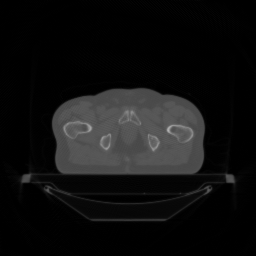

Refer to caption

(a) Ground truth

(b) PDFP, PSNR= 44.94

(c) SPDFP, PSNR= 37.29

(d) SVRG-PDFP, PSNR= 44.98

(e) OPG-ADMM, PSNR= 37.45

(f) SVRG-ADMM, PSNR= 43.82

Figure 5: Reconstructed image (averaged) with different methods over 10 repetitions.

FIG 3 give the results of the peak signal-to-noise ratio (PSNR) of the reconstructed images over time on two devices. It can be seen that stochastic algorithms without SVRG can not get high PSNR comapred to that with SVRG and the full batch PDFP. The performance of SVRG-PDFP is as good as PDPF with the device TITAN RTX while SVRG-PDFP behaves the best with the devices with less cores. FIG 4 record the computational time of different algorithms when PSNRs reach 30,35,37,433035374330,35,37,43 on the two different devices. We can see that when the computational resource is powerful (with many parallel cores), the full-batch PDFP can be highly parallized and the stochastic algorithm does not gain in general. However, when the cores number is not very high, stochastic algorithms with SVRG are beneficial compared to deterministic algorithms. FIG 5 gives the reconstructed images with different algorithms and we can see that the one with SVRG-PDFP achieves the highest PSNR as the full batch PDFP.